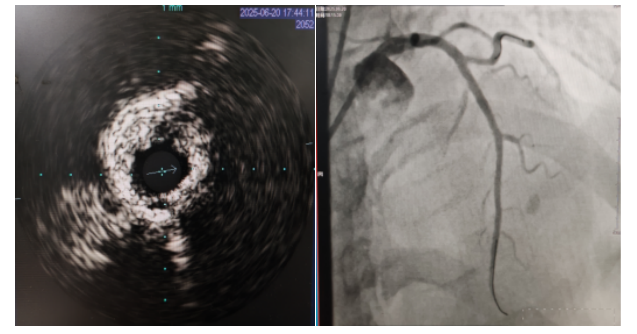

術中,趙慶禧主任醫(yī)師、雷剛副主任醫(yī)師運用IVUS血管內超聲技術評估,發(fā)現(xiàn)患者前降支、對角支0.1.1型真性分叉病變,前降支近中段嚴重鈣化、成角并99%狹窄,對角支近段嚴重鈣化并99%狹窄,傳統(tǒng)冠狀動脈旋磨術容易引起冠狀動脈穿孔,決定采用沖擊波球囊技術即血管內沖擊波鈣化碎裂術對患者嚴重鈣化的血管進行介入治療。通過球囊低壓擴張,向血管病變處發(fā)射非聚焦、低能量、脈沖式的沖擊波,對前降支及對角支進行了連續(xù)5個周期沖擊波脈沖治療,安全地碎裂淺、深層鈣化,原本看似堅不可摧的環(huán)形鈣化區(qū)逐漸顯現(xiàn)出了裂痕,多處關鍵位置發(fā)生了斷裂,充分預處理后于前降支近中段串聯(lián)植入支架3枚,對角支植入藥物球囊,術后造影見血管病變處狹窄完全消失,支架膨脹完全,貼壁良好,各項生命體征平穩(wěn),手術非常成功,患者返回心血管內科病房繼續(xù)治療,并于4天后順利出院。